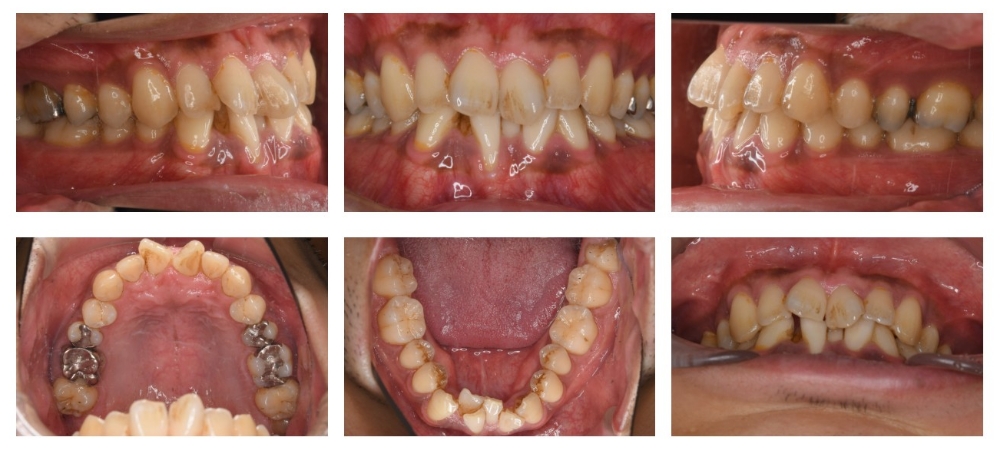

症例

| 主訴 | ガタガタ |

| 年齢/性別 | 30代 / 男性 |

| 抜歯部位 | 非抜歯 |

| 使用装置 | ブラケット(ラビアル) |

| 治療期間 | 1年7ヶ月 |